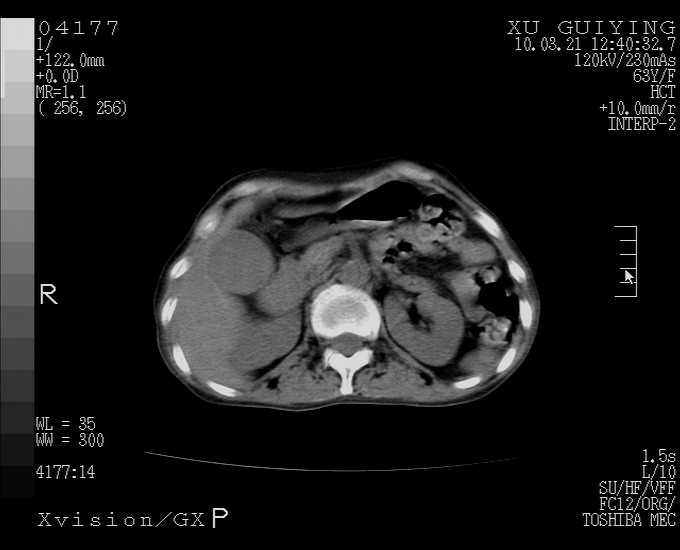

怎么没有增强呢?胆囊那么大,密度有些高啊。

慢性胆囊炎,胆囊占位不排除,建议增强或彩超。

考虑胆囊炎 不除外泥沙样结石

胆囊体积增大,胃窦壁增厚

胆囊体积增大,密度不均匀,结石不除外;胃壁增厚,考虑胃癌,建议增强。

胆囊体积增大,密度增高,较均匀,外缘也较光滑,应考虑胆囊炎。因为胃未充盈,不好说壁增厚。肝左叶及脾门处见低密度灶,有可能是血管瘤,不排除囊肿。建议超声检查或强化。